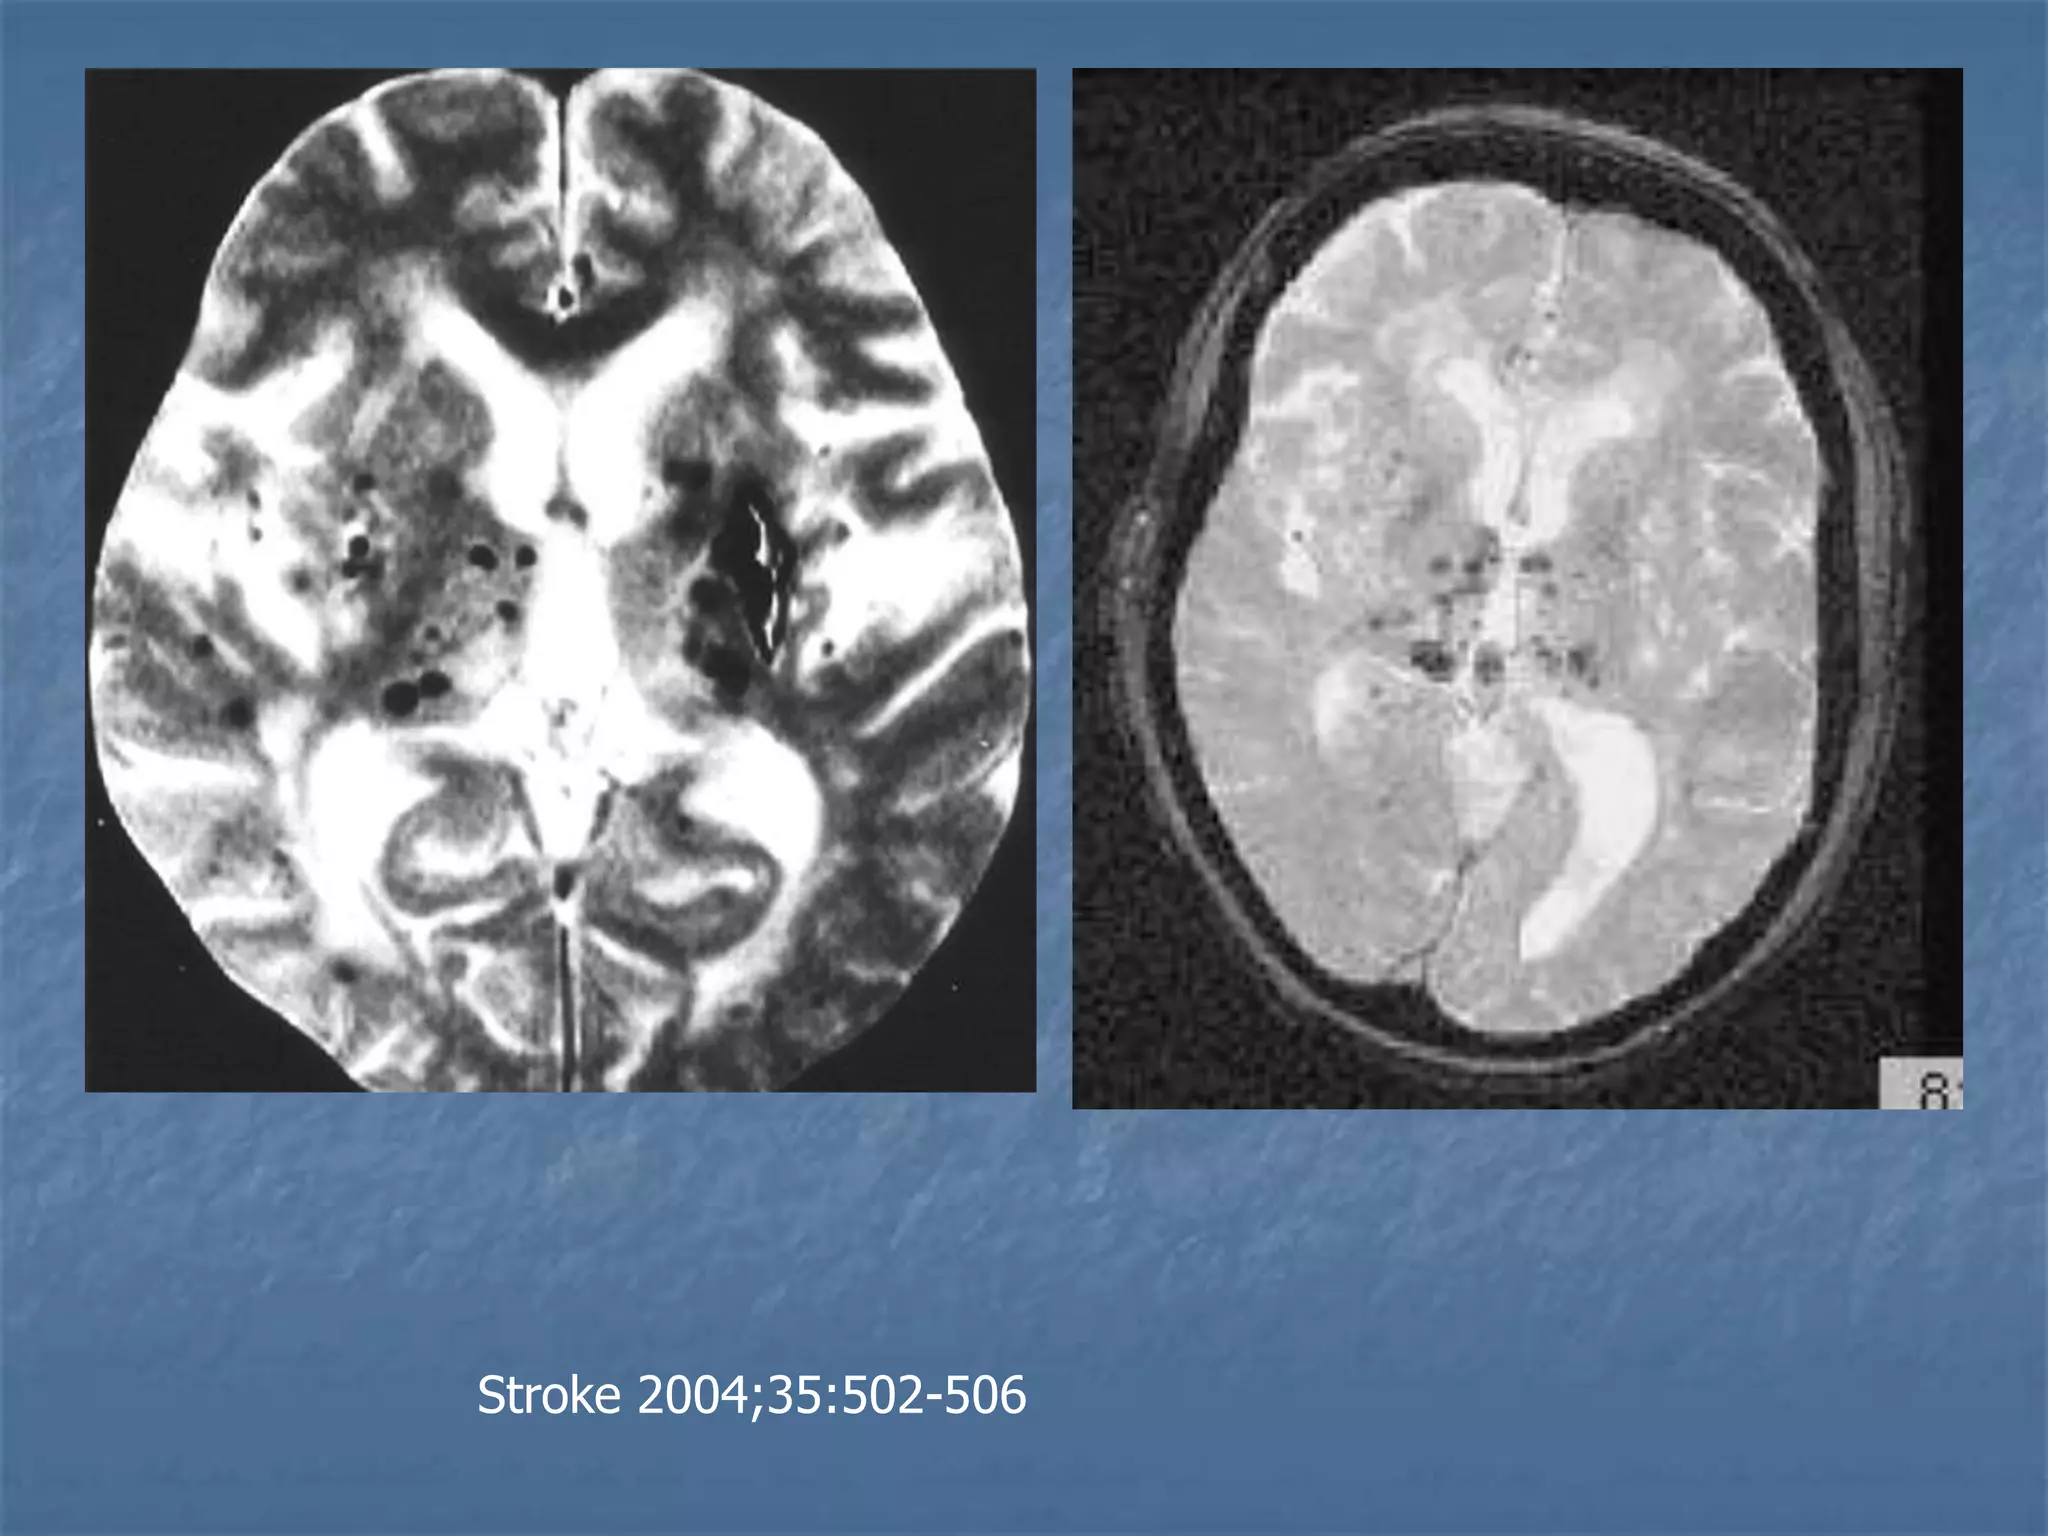

Lacunar Infarcts

Diffuse Axonal Injury

Stroke 2004;35:502-506